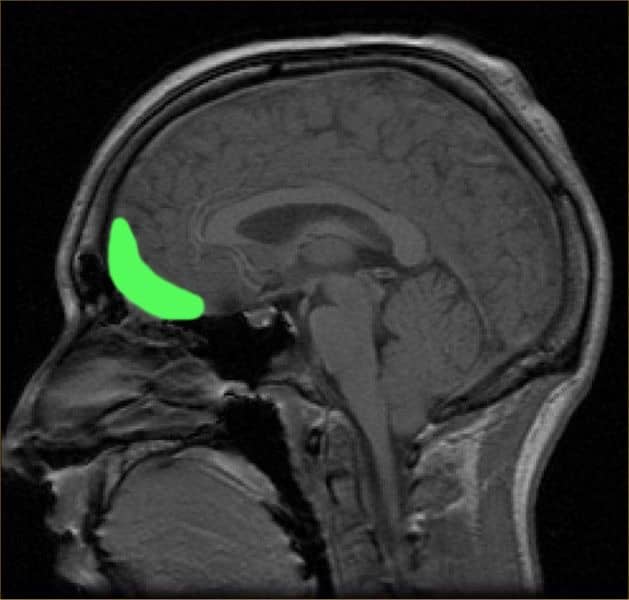

La glándula pituitaria del tamaño de un guisante se encuentra en la base del cerebro, en la silla turca. A pesar de su pequeño tamaño, es el principal órgano endocrino, regulando casi todas las demás glándulas endocrinas.

Los adenomas hipofisarios son comunes y se pueden detectar en aproximadamente el 20 % de las personas mediante imágenes de resonancia magnética. Estos son tumores que surgen en las células de la glándula pituitaria. En el 99,9% de los casos, al examen histológico son benignos, pero pueden tener un curso maligno.